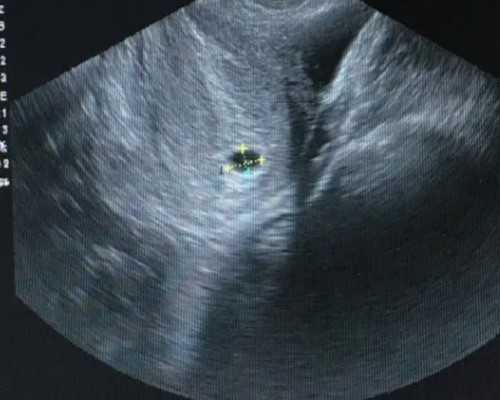

人工授精手术全过程